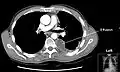

A pleural effusion appears as an area of whiteness on a standard posteroanterior chest X-ray.[15] Normally, the space between the visceral pleura and the parietal pleura cannot be seen. A pleural effusion infiltrates the space between these layers. Because the pleural effusion has a density similar to water, it can be seen on radiographs. Since the effusion has greater density than the rest of the lung, it gravitates towards the lower portions of the pleural cavity. The pleural effusion behaves according to basic fluid dynamics, conforming to the shape of pleural space, which is determined by the lung and chest wall. If the pleural space contains both air and fluid, then an air-fluid level that is horizontal will be present, instead of conforming to the lung space.[16] Chest radiographs in the lateral decubitus position (with the patient lying on the side of the pleural effusion) are more sensitive and can detect as little as 50 mL of fluid. Between 250 and 600mL of fluid must be present before upright chest X-rays can detect a pleural effusion (e.g., blunted costophrenic angles).[17]

Chest computed tomography is more accurate for diagnosis and may be obtained to better characterize the presence, size, and characteristics of a pleural effusion. Lung ultrasound, nearly as accurate as CT and more accurate than chest X-ray, is increasingly being used at the point of care to diagnose pleural effusions, with the advantage that it is a safe, dynamic, and repeatable imaging modality.[18] To increase diagnostic accuracy of detection of pleural effusion sonographically, markers such as boomerang and VIP signs can be utilized.[19]

Massive left-sided pleural effusion (whiteness) in a patient presenting with lung cancer. -